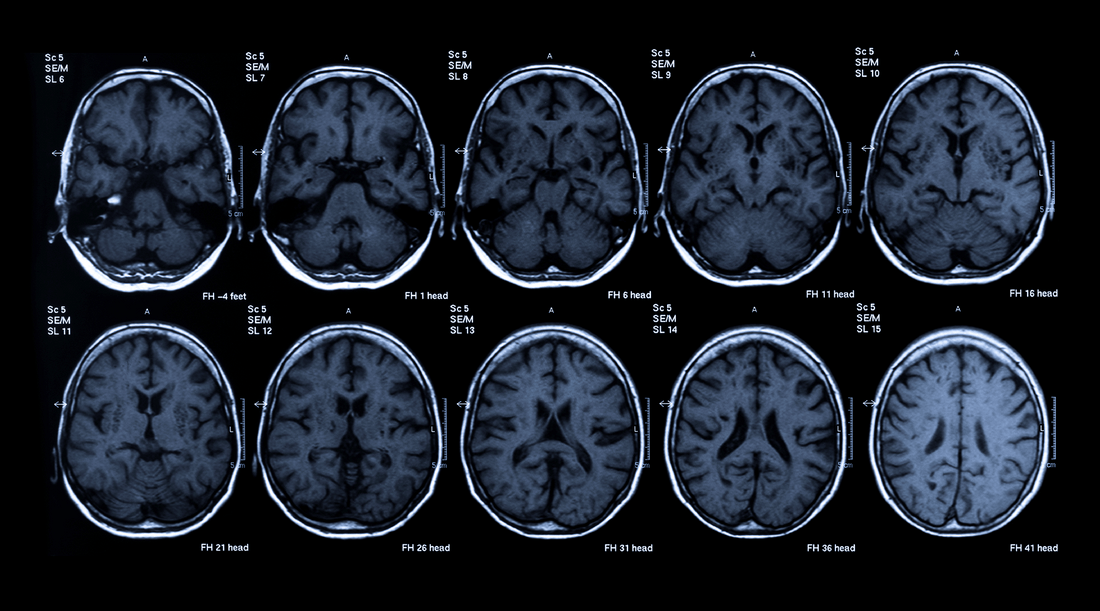

Based on finding B12 deficiency in people with memory impairment, the OPTIMA study leaders measured the rate of shrinkage of the brain in normal volunteers over a period of five years, performing brain scans every year to accurately measure the rate of shrinkage of the whole brain.

Over the course of two years, the B-vitamin complex in Matter measurably slowed the rate of brain atrophy by 30%, and in certain brain regions involved in visuospatial learning and spatial long-term memory, the rate of gray matter atrophy was slowed by an average of 86%.

Figure 2. Regions where significant grey matter atrophy was detected in placebo and B-vitamin groups over the two-year study period. *Not intended to indicate the amount of atrophy in any region.

The conclusion from the study, which concluded in 2009, was clear: The accelerated rate of brain atrophy in elderly with mild cognitive problems can be slowed by treatment with homocysteine-lowering B vitamins.